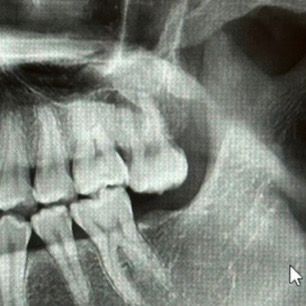

제2대구치 큰어금니가 없는데 임플란트 대신 발치하고싶어요

원래 아래쪽 큰어금니가 없어서 치과에서는 임플란트를 하라고 했는데요..

그래서 일단 냅뒀더니 위쪽 큰어금니가 계속 자라면서 양치도 잘 안돼고 좀 아파져서요ㅜ 가끔 아래쪽 잇몸도 부아오르고

엑스레이가 한 반년전이고 사진이 지금이에요

• 2번 째 사진

1. 말씀하신 것처럼 지금 왼쪽 맨 뒤 어금니는 아래와 맞닿는 치아가 없어서 위에 치아는 계속 정출되고, 잇몸 염증 유발합니다.

2. 별다른 처치 없이 뺄 경우 이제 왼쪽은 큰 어금니 위, 아래로 1개씩만 가지고 생활하시는 거고 아주 큰 문제는 없으나 아무래도 저작력이 떨어집니다. 남은 어금니 한개가 힘을 많이 받고, 일을 많이 하다보면 또 금방 망가질 수 있습니다.

3. 이 뺀 자리는 이제 잇몸과 잇몸뼈가 흡수되기 시작하여 뼈가 얇아집니다. 많이 지체되면 임플란트 심기 어려운 환경이 될 수도 있습니다.